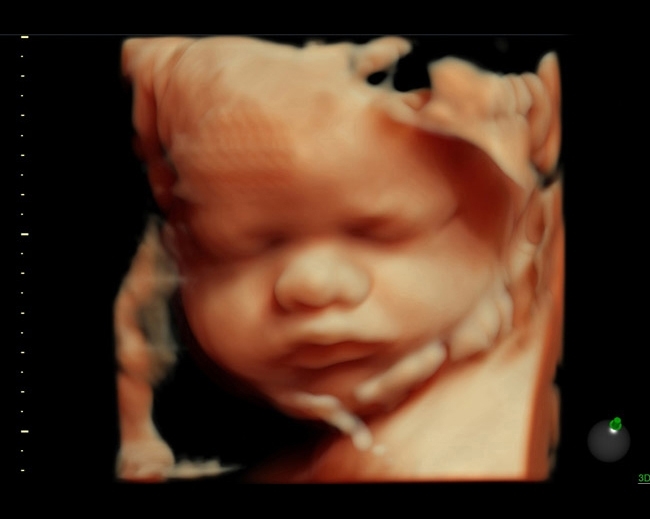

Poze 4d bebelusi. Iti recomandam sa citesti cele mai interesante si relevante articole pe tema poze frumoase bebelusi. Poze cu bebelusi fete. Care vi se pare cel mai frumos. Ecografia 4d adauga timpul ca a 4 a dimensiune arata imagini actualizate in mod continuu in timp real asemanatoare unui film.

Micii fotografi ai viitorului. Poza bebelus 17 noiembrie este ziua internationala a prematuritatii. Benefiicile 3d si 4d identifica mai precis anomaliile fetale mai ales ale fetei inimii membrelor tubului neural si scheletelui. Stirivirale a pregatit pentru voi 105 poze cu copii si bebelusi super amuzanti care au foarte mult par.

Aceasta metoda de diagnostic a evoluat foarte mult si din punct de vedere tehnic. Micii bebelusi par ca au muncit pana la epuizare pentru a surprinde cele mai frumoase fotografii. Voi ce experiente ati avut cu copii vostri. Ziua internationala a prematuritatii.